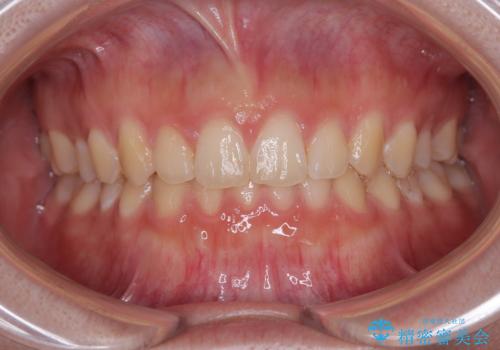

歯冠長延長術を行ったことで、自然な形態かつ清掃性の高いセラミッククラウンを装着することができました。

全顎的に治療を行ったため、治療期間も費用も負担は大きくなりましたが、統一感のある仕上がりとなりました。